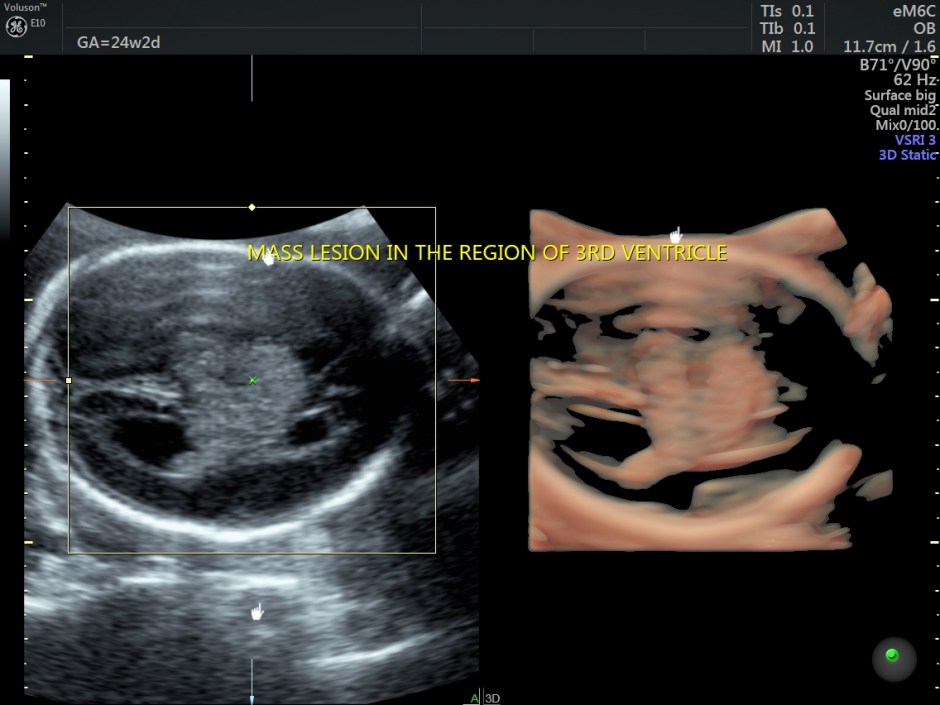

A careful look at the 3rd ventricle shows a solid mass.

Some reconstructed images are given below.